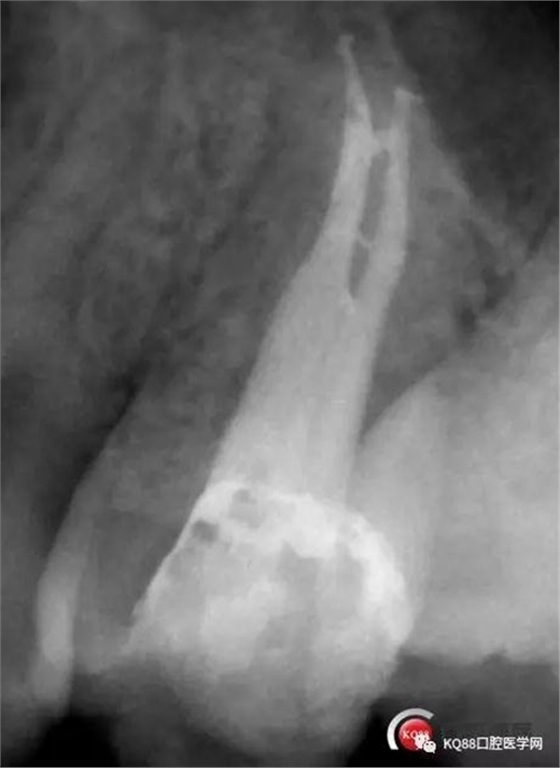

這兩張角度的截圖告訴我們這個牙齒一個典型的Y型根管,髓腔非常巨大,從根管口看,貌似一個根管口,但是根管銼下去以后,會兩個方向角度的分開。因?yàn)槲覀儸F(xiàn)在都是常規(guī)的機(jī)擴(kuò)與熱牙膠充填,建立直線根管口的暴露就變得非常重要,必須直線視野下操作,機(jī)擴(kuò)才不會發(fā)生扭曲折斷。目前市面上的根管銼有很多,M3,S3等,而此次我使用的是歐羅德卡PLEX軟銼,因?yàn)槭强谇?8贈送我的,所以我就先嘗試的使用了一下,我不會單方面的去評價(jià)比別的好,我覺得預(yù)備方法對了,都會很不錯,只能說一句這個用起來軟銼對后牙的預(yù)備確實(shí)不錯。根管預(yù)備,常規(guī)我都會先C銼疏通,如果直接15號很有可能會在根尖方形成臺階,以后就很難再下去了,當(dāng)C銼到達(dá)根尖孔后,予以初步測量長度,在用疏通機(jī)擴(kuò)針通入,然后一步步規(guī)范化開始,逐級預(yù)備,一個簡單的經(jīng)驗(yàn),如果當(dāng)使用的銼不容易到達(dá)根尖時,不要著急,用上一號,繼續(xù),再回來,就可以了,不然形成臺階,就很難操作了,常有人會覺得擴(kuò)根時,突然發(fā)現(xiàn),下不去了,排除斷針的可能性的話,臺階是最重要的,擴(kuò)根時,1%次氯酸鈉變沖洗,變預(yù)備,防止碎屑推出根尖孔,我沖洗常使用1%次氯酸鈉與蒸餾水,再充填前,會使用EDTA沖洗液去除根管壁油污。

當(dāng)我第一次完成操作后,再次拍了一個插針片,發(fā)現(xiàn),距離根尖孔有1.5mm,書上說的是2mm安全區(qū),可能如果隨意點(diǎn),就直接充填了,我想說明的是,我們做根管,千萬不要馬虎,不要湊合,一定嚴(yán)謹(jǐn)?shù)膽B(tài)度,于是我重新再回到C銼,再開始耐心的預(yù)備,完成之后,再拍攝了插針片。

此次明顯可以看見根尖分開了兩個根尖孔,根管治療永遠(yuǎn)就只是那一點(diǎn),如果都只是隨便做一下,我相信,沒有復(fù)雜的牙齒,根管治療都會很簡單,態(tài)度決定一切,我不敢說我做的會很好,但是我會靜下心來,慢慢操作,這樣才能做得對的起自己和患者。于是根充完成,再次拍攝。

Y形態(tài)變形成了,根間支也明顯出現(xiàn),充填嚴(yán)密,雖然根管治療的成功率不是一百,但是我們盡可能把那一點(diǎn)做到位,往往結(jié)果可能會很驚人,如果我在第一次就充填了,可能也不會有什么錯誤,但是態(tài)度就已經(jīng)輸了,我們基層做根管不會像武大等那么規(guī)范,但是也希望可以向其靠攏,一個好的根管,上面才能有美的修復(fù)。